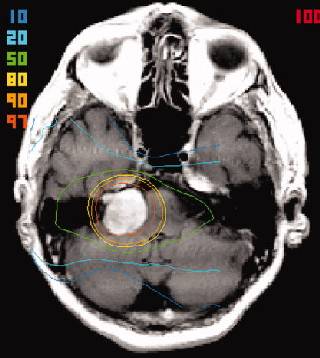

The FSRT technique involved the use of a relocatable stereotactic Gill-Thomas-Cosman (GTC) frame and multiple non-coplanar converging arcs of 6-MV photon beam, utilizing the Radionics (Burlington, MA) X-Knife radiation treatment planning system with MR-CT image fusion software. The gross tumor volume (GTV) was defined as the area of contrast enhancement on T1-weighted MRI, with the planning target volume (PTV) including a further 1-2 mm safety margin added to account for variance within the treatment planning system. The accuracy of this system has been previously documented as 0.4 mm. The total dose was 50 Gy in 25 daily fractions over 5 weeks, prescribed to the 95% to 100% encompassing isodose.